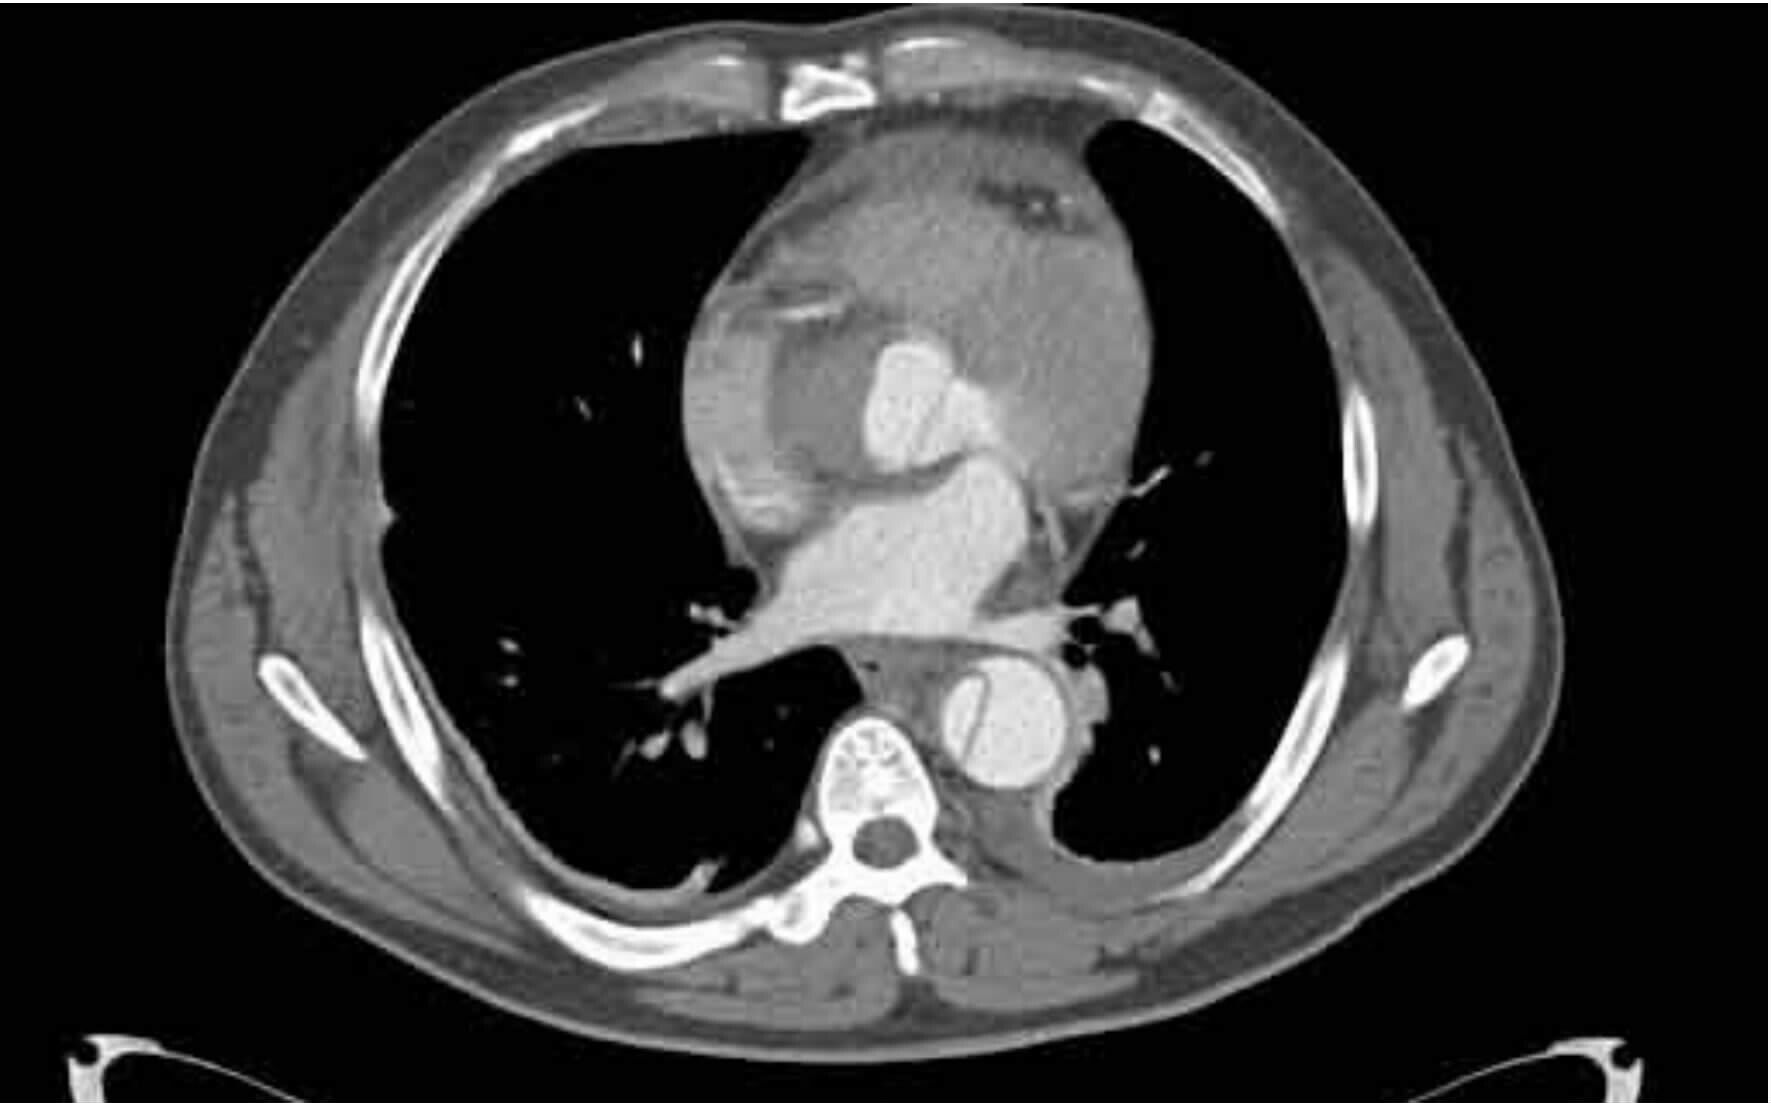

2 结果37例钝性胸主动脉损伤,CTA征象表现为内膜瓣、轮廓异常、血栓、动脉收缩、假性动脉瘤、主动脉夹层6种情况。①内膜瓣:内膜瓣为增强的主动脉管腔内可见一个或多个弧形弱化区(图 1)。②主动脉轮廓异常:表现为主动脉管壁或轮廓不规则,圆形的主动脉横切面发生变化,(图 2)。③假性动脉瘤:指主动脉壁破裂出血,形成主动脉壁外的血肿,主动脉管腔与不规则瘤腔结合处呈锐性边缘(单侧或双侧),(图 3)。④主动脉夹层:内膜片和主动脉真假两腔形成是诊断夹层动脉瘤的基本征象。内膜片将血管分为真假两个腔隙。增强早期真腔密度高于假腔,随时间延迟,假腔密度逐渐增高,假腔密度可等于或高于真腔,(图 4)。⑤动脉收缩表现为损伤节段主动动脉直径小于正常节段动脉直径(图 5)。⑥血栓;主动脉腔内息肉样低密度区(图 6)。本组37例钝性胸钝性胸主动脉损伤患者,CTA征象存在内膜瓣34例(91.8%),主动脉轮廓改变或腔异常37例(100%),动脉收缩17例(45.9%),主动脉夹层10例(27.0%),假性动脉瘤21例(56.7%),血栓1例(2.7%)。

| 图 4 主动脉降部损伤夹层征象 Figure 4 Dissection sign of descending aortic injury |